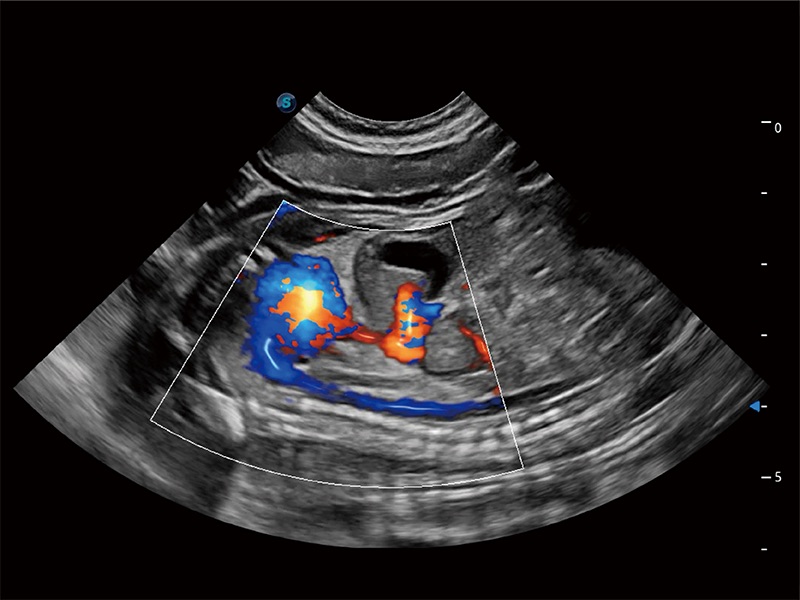

ProPet 80 配备了丰富的心脏探头群、先进的成像技术和专业的心脏测量工具,可帮助动物医生为不同体型和生理结构的动物提供心脏和心肌功能的全面评估。

实时用颜色表示心肌组织运动,观察和定量组织的运动情況,对快速检测与评估心肌的灌注和活性、电传导及心肌收缩和舒张功能等均能提供重要的诊断信息。

能够增加心肌组织与血流之间的区别。对于心脏扫查困难的动物,可提供更好的心内膜边界的显示。